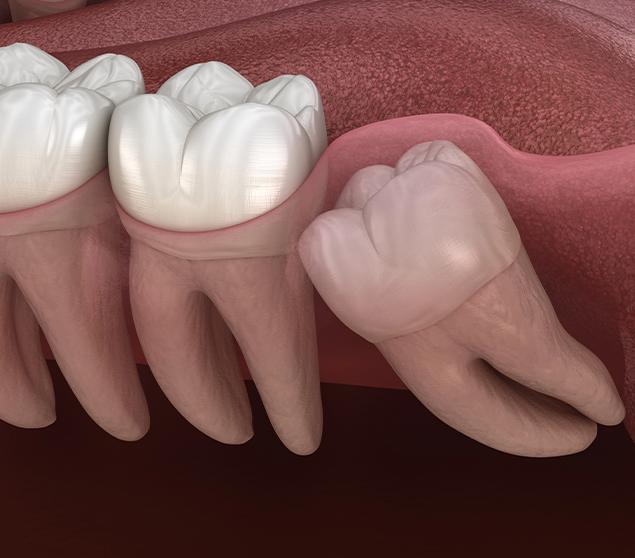

Before recommending extraction, our dental team completes a thorough assessment, which may include a clinical examination and dental X-rays. Findings and treatment options are reviewed clearly so you can make informed decisions about your care.

If wisdom tooth extraction is recommended, the procedure and aftercare expectations are explained in advance. Our focus is on clear communication and patient comfort throughout the entire process.